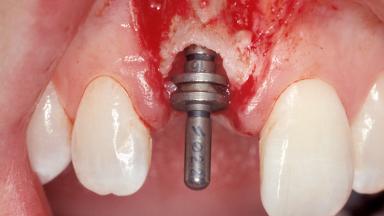

Type of Implants One-Piece|Reduced-Diameter

Attachment One-Piece|Reduced-Diameter

Placement Protocol Immediate implant placement

Tooth Site Maxillary incisor or canine

Socket Morphology Single-root socket

Socket Integrity Sufficient, with intact bone walls